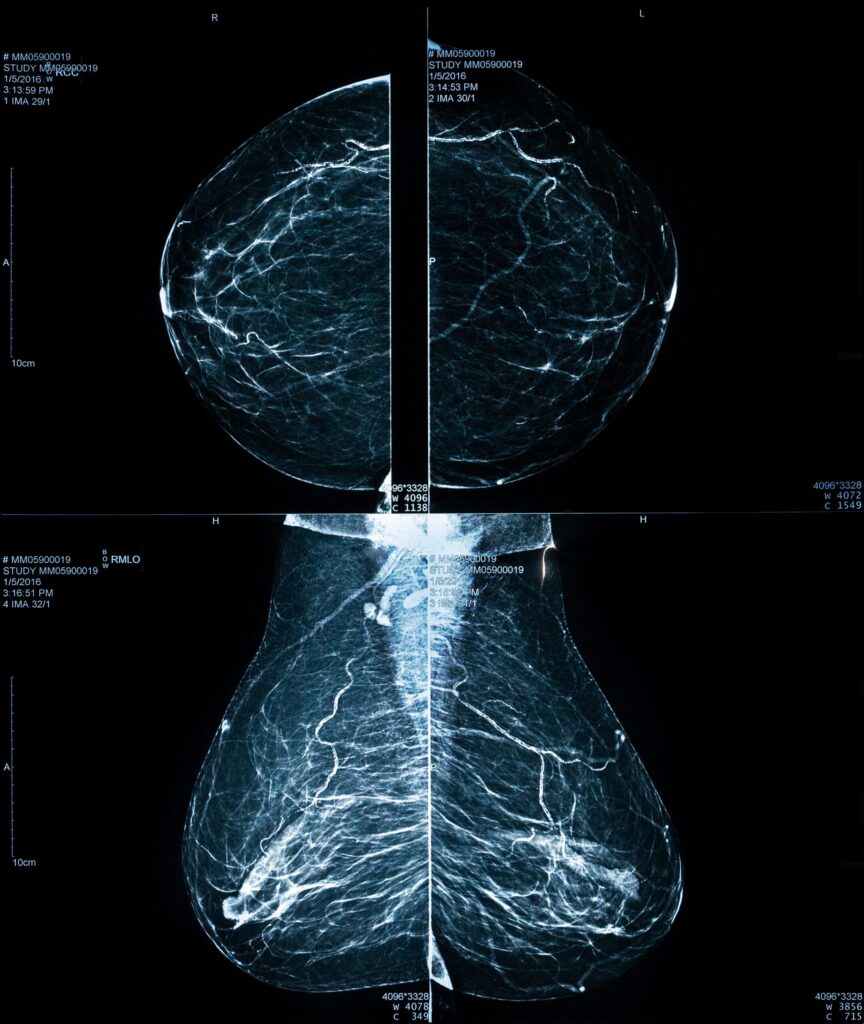

Com quantos anos devo fazer mamografia? Saiba aqui

Você já se perguntou qual é o momento certo para fazer sua primeira mamografia? Ou ficou em dúvida sobre cada quanto tempo precisa repetir o exame? Essas são perguntas que recebo diariamente no consultório, e a resposta pode ser o primeiro passo para cuidar da sua saúde com informação e segurança. A mamografia é, sem […]

Mamografia: Quando Fazer e Por Que é Essencial

A mamografia é um exame que gera muitas dúvidas e, para algumas mulheres, até um certo receio. No meu consultório, percebo que a falta de informação clara pode transformar um ato de cuidado em uma fonte de ansiedade. Vejo diariamente o impacto positivo deste exame na vida das mulheres – desde a tranquilidade de um […]

Mamografia Dói? Como Reduzir o Desconforto do Exame

Sei que muitas mulheres sentem um frio na barriga só de pensar nele, principalmente por causa da fama de ser desconfortável ou doloroso. Mas estou aqui para desmistificar essa ideia e mostrar por que esse exame é tão importante e como podemos torná-lo uma experiência mais tranquila para você. A mamografia é, sem dúvida, nossa […]